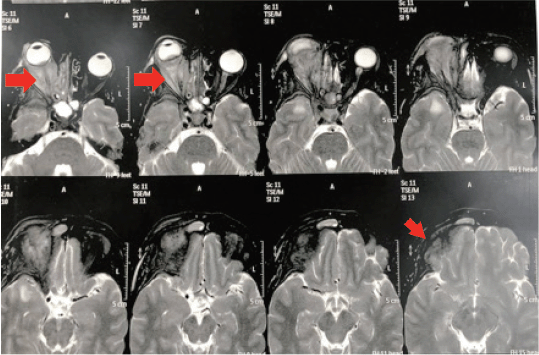

After a multidisciplinary discussion, she started a combination chemotherapy of cisplatin and gemcitabine with a stationary course followed by Anastrozole. Three months later, the patient experienced further progression of her symptoms, in the form of ulceration, severe pain and pus discharge. The patient received palliative RTH at the dose of 30 Gy in ten fractions with no response (Figures 2 and 3). The patient was deceased 1 month later upon the deterioration of the general condition and further disease progression.

Figure 2. MRI brain and orbit showed significant increase in the previously described right recti muscles thickness with heterogeneous post-contrast enhancement. There is subsequent proptosis and posterior ocular coat mass lesion just above the optic disc with significant enhancement of all posterior ocular coats. There is extra-orbital spread, and intra-cranial extra-axial leptomeningeal enhancement at the right frontotemporal region.